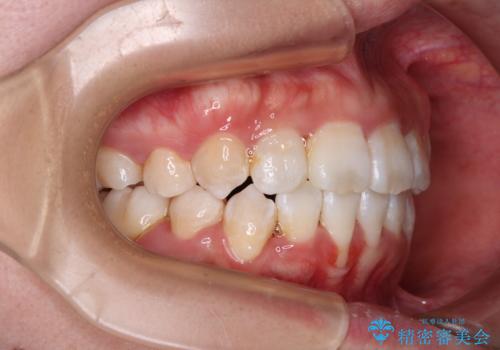

- 飛び出した上顎の前歯と八重歯を気にして来院された患者様です。

口元を積極的に引っ込めるために、上下左右の小臼歯計4本を抜歯することとしました。

舌の突出癖が強いため、しっかりと口元を引っ込めるため、舌のトレーニングをしっかりと行いながら矯正治療を行うこととしました。